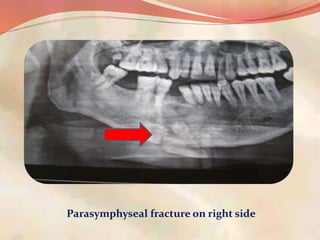

Parasymphyseal fracture on right side.

35 years male patient

presented with fracture

mandible with soft tissue

injury following RTA.